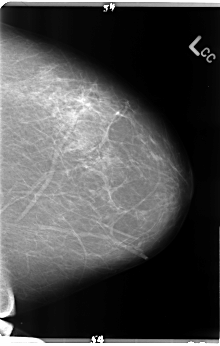

ics_version 1.0 filename B-3144-1 DATE_OF_STUDY 25 7 1997 PATIENT_AGE 43 FILM FILM_TYPE REGULAR DENSITY 2 DATE_DIGITIZED 5 5 1998 DIGITIZER LUMISYS LASER SEQUENCE LEFT_CC LINES 4832 PIXELS_PER_LINE 3080 BITS_PER_PIXEL 12 RESOLUTION 50 NON_OVERLAY LEFT_MLO LINES 4744 PIXELS_PER_LINE 3112 BITS_PER_PIXEL 12 RESOLUTION 50 NON_OVERLAY RIGHT_CC LINES 4704 PIXELS_PER_LINE 2904 BITS_PER_PIXEL 12 RESOLUTION 50 OVERLAY RIGHT_MLO LINES 4744 PIXELS_PER_LINE 3176 BITS_PER_PIXEL 12 RESOLUTION 50 OVERLAY |